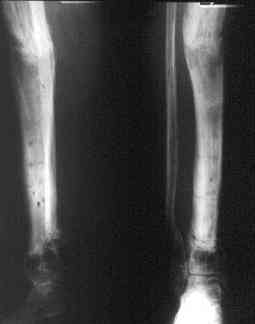

исправлена ось и возмещен дефект. В результате восстановление тыльной флекcии стопы и функции конечности. #9;#10;#11